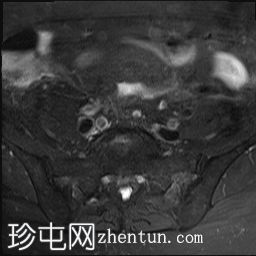

非脂肪抑制像

该T2脂肪抑制磁共振成像显示右髂血管旁有一管状结构,终止于回盲部。